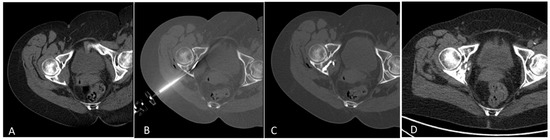

2.2. Radiofrequency Ablation (RFA) and Cementoplasty Procedure

| 70—W | Breast | left acetabulum | 35 × 30 × 25 mm | 2 1 | 7 | 3 0 0 0 0 | 7 cc | leakage cement | CT |

| 59—W | Breast | left acetabulum + quadrilateral lamina | 34 × 34 × 18 mm | 3 2 | 8 | 4 4 2 0 0 | 5 cc | none | CT |

| 55—M | Renal cell carcinoma | left acetabulum | 18 × 15 × 25 mm | 2 1 | 6 | 1 1 0 0 0 | 4 cc | none | CT |

| 62—W | Breast | right acetabulum | 20 × 20 × 32 mm | 2 1 | 5 | 2 1 1 0 0 | 7 cc | none | CT |